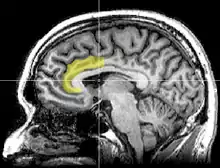

Dans une étude utilisant l'imagerie cérébrale (IRM fonctionnel) et publiée dans la revue Science en 2003, Naomi Einsenberger et ses collaborateurs ont montré que le sentiment d'exclusion sociale, crée artificiellement pendant l'expérience, activait des zones du cerveau similaires à celles activées lorsque l'individu éprouve une douleur physique[16],[17]. Leurs recherches sur ce problème ont continué à indiquer l'implication du cortex cingulaire antérieur dans la douleur (ou souffrance) engendrée par le rejet des pairs ou d'autres conditions d'exclusion sociale contrôlées expérimentalement[18]. Ces résultats sont discutés par les spécialistes en neurosciences sociales et leur interprétation n'est pas consensuelle[19].